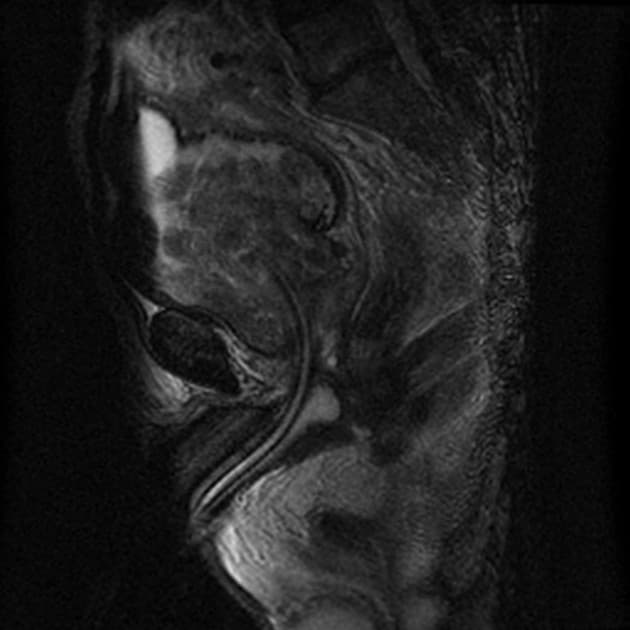

Sagittal T2

MRI•Sagittal T2•1 / 30

- Tổn thương giảm tín hiệu T2 (T2 hypointense), giới hạn không rõ, dạng gai (spiculated), kích thước 7 x 5 mm, có hạn chế khuếch tán (restricted diffusion) và tăng quang sớm ở thì động mạch (early arterial enhancement), nằm ở vùng trung tâm/mũi tuyến, tại vùng ranh giới giữa PZpl/pm bên phải, gợi ý tổn thương PI-RADS 4 (suggestive of a PI-RADS 4 lesion).

- Các nốt tăng tín hiệu T2 (T2 hyperintense), giới hạn rõ (well-circumscribed), đặc trưng của tăng sản lành tính, kích thước tối đa 18 mm tại vùng TZ, phù hợp với nhóm PI-RADS 1 (consistent with PI-RADS 1 category).

- Các nếp gấp túi tinh trái tạo hình ảnh giả giống nốt lành tính vùng PZa trái (benign left PZa nodul) ở mức đáy.

- Thoát vị vào trong bàng quang (endovesical protrusion) tại vùng đáy tuyến.

Trường hợp này mô tả một tổn thương PI-RADS 4 ở vùng ngoại vi tại mức trung tâm/mũi tuyến, đặc trưng bởi hình dạng giảm tín hiệu trên T2, biên dạng gai, hạn chế khuếch tán trên DWI và tăng quang sớm ở thì động mạch – những dấu hiệu gợi ý mạnh đến ung thư tuyến tiền liệt có ý nghĩa lâm sàng. Mặc dù các bệnh lý lành tính như viêm tuyến tiền liệt mạn tính hoặc tổn thương teo hậu quả có thể bắt chước ung thư, nhưng sự kết hợp các hình ảnh này đòi hỏi phải sinh thiết định hướng để xác nhận bằng mô học. Ngược lại, các nốt ở vùng chuyển tiếp với đặc điểm tăng sản lành tính điển hình được phân loại là PI-RADS 1, phản ánh nguy cơ rất thấp. Đánh giá PI-RADS chính xác giúp định hướng quyết định lâm sàng, giảm thiểu sinh thiết không cần thiết đồng thời đảm bảo phát hiện các khối u ác tính.